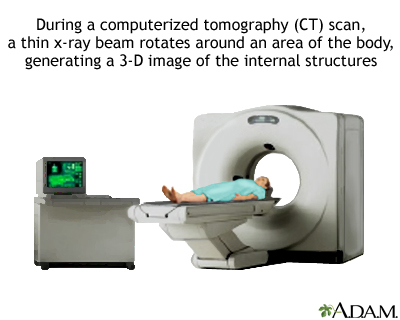

Imaging Tests

Ultrasound or computed tomography (CT) scan may be used to determine the extent of scarring in the liver and to check for signs of liver cancer. A newer imaging method called transient elastography measures liver stiffness and may provide a non-invasive alternative to liver biopsy to demonstrate the presence of fibrosis or cirrhosis. This technique is most often done using ultrasound. A score will be reported to reflect the severity of fibrosis thought to be present. The METAVIR score is widely used reporting five stages, F0 (no fibrosis) through F4 (cirrhosis).